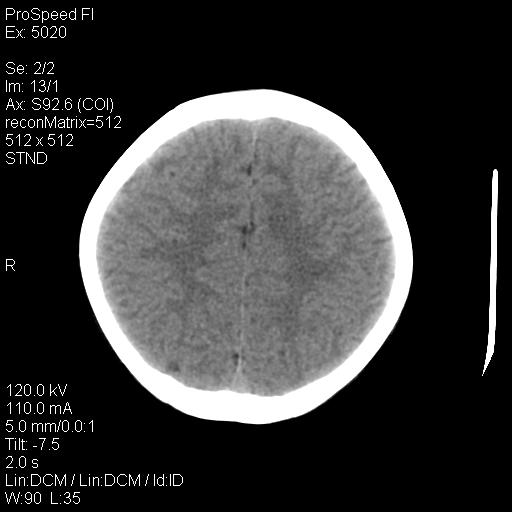

标题: PED1637:M 6Y 顶部无痛性包块两月。 [打印本页]

标题: PED1637:M 6Y 顶部无痛性包块两月。

2、颅骨局部缺失,边缘光滑、整齐

颅骨为好发部位,生长缓慢,常位于顶骨、枕骨及颞骨,表现为颅骨缺损,呈圆形或椭圆形,边界清,无硬化